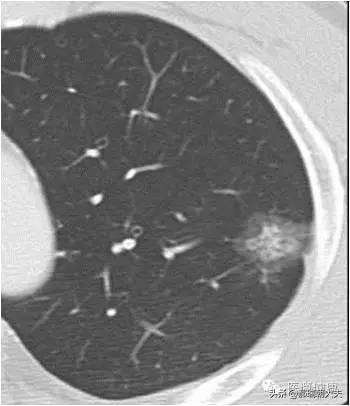

健康診断への意識が高まるにつれ、肺結節が発見される人が増えている。肺結節とは画像診断の用語で、肺結節の画像上の定義は、肺実質に完全に囲まれた、境界明瞭な小さな病変(直径≤30mm).結節の形態は、固結または亜固結に分類される。亜固結はさらに、純粋なすりガラス結節と部分的な固結に分類される。直径30mmを超える病変は結節ではなく腫瘤であり、悪性の可能性が高い。

現在受け入れられている肺結節の定義は、直径3cm以下の限局性、円形、高密度、固形または亜固形の肺影である。 近年、低線量CTによるスクリーニングを受ける人口が増加するにつれて、孤立性肺結節に加えて多発性肺結節が検出される割合がかなり増加している。多発性肺結節は多くの場合、1個の肺結節と1個以上の小結節として現れる。多発性肺結節は2個以上の病変として定義される。多発性肺結節を有する患者は、外科的に確認され、臨床的に重大な注意を要する早期肺癌または前癌病変の複数の発生源を有する可能性がある。

肺結節:肺の組織に現れる病変である。直径30mm以下の円形または不規則な病変で、正常な肺組織に囲まれていることが多い。医用画像では「肺の高密度陰影」と表現される。肺小結節は単結節または多結節で、境界が明瞭なものと不明瞭なものがある。